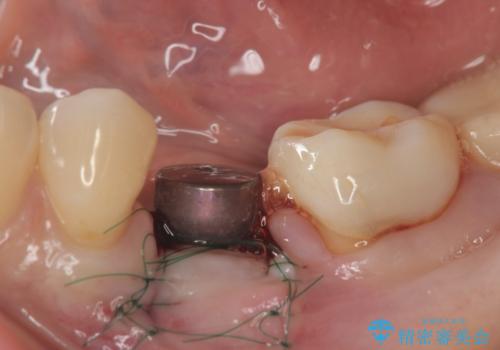

- 残していた乳歯がぐらつき始め、抜去ののちのインプラント治療を希望され来院されました。

乳歯を抜去して歯ぐきの状態が落ち着いたのち、骨の増成を伴うインプラント治療を行い機能の回復を図ります。

残念ながらぐらつきが大きくなり、残すことが難しくなり抜去したのちインプラントを用いて咬合機能の回復をしっかりと行いました。